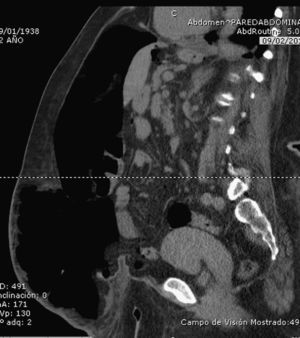

After 2 weeks of insufflation, the abdominal wall was examined by evaluating the muscle tension exhibited on the side of the abdomen in order to verify that this was becoming sufficiently relaxed. In some cases, the patients underwent a control CT scan (Fig. 4), but this was not done systematically because the follow-up of the progression was mainly clinical. Patients were considered fit for surgery when the lateral abdominal musculature was completely distended.